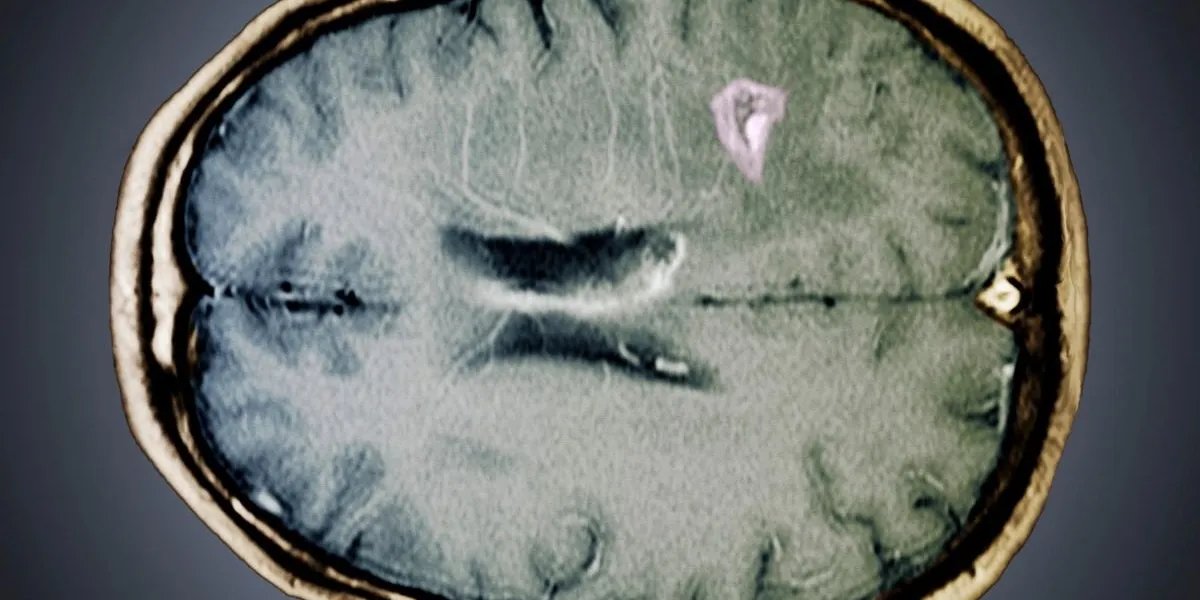

Os acidentes vasculares cerebrais têm muitas causas, mas a maioria está relacionada a fatores de risco cardiovascular de longo prazo, como hipertensão e outras condições vasculares. Três hábitos aparentemente inócuos ainda podem estar ligados a uma condição mortal.

Embora os gatilhos não representem uma ameaça para a maioria dos indivíduos, o médico explicou que ocasionalmente podem desencadear uma perigosa cadeia de eventos que culmina num acidente vascular cerebral.

Seu conselho se concentra na proteção dos delicados vasos sanguíneos que fornecem oxigênio ao cérebro. O primeiro hábito contra o qual o Dr. Chen alerta é usar pistolas de massagem na região do pescoço.

Esta área contém as artérias carótidas nas laterais e as artérias vertebrais nas costas, ambas importantes para levar sangue oxigenado ao cérebro.

A pressão forte e rápida aplicada a esta área sensível pode danificar o revestimento das artérias, o que pode levar a uma dissecção, um pequeno rasgo na parede do vaso.

Quando ocorre uma ruptura, o corpo responde formando um coágulo que pode se desalojar e viajar até o cérebro, desencadeando um derrame.